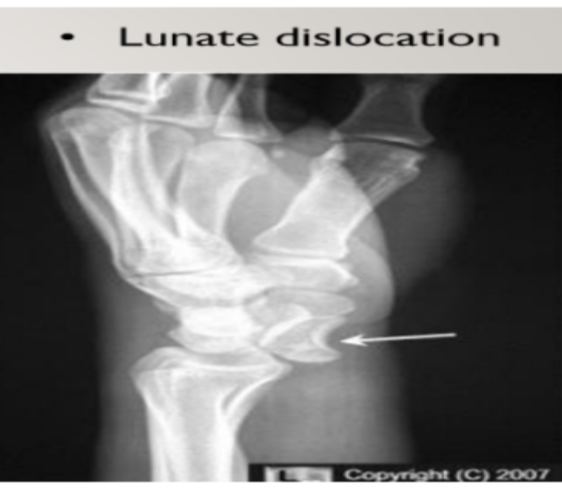

During a scaphoid fracture, there’s usually a lunate dislocation. Which nerve is compressed during this location?

A

Median nerve